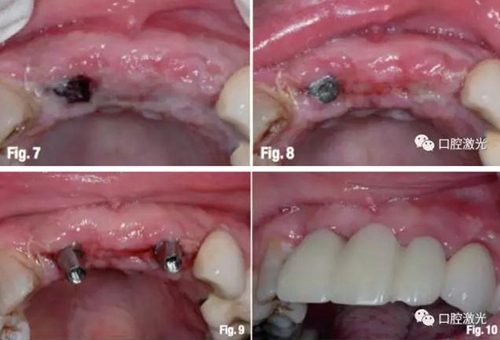

患者沒有發(fā)現(xiàn)有任何其他并發(fā)癥狀。手術(shù)2天后,可觀察到纖維蛋白層就已經(jīng)完整覆蓋傷口(圖7)。22位置的愈合基臺已經(jīng)被新生的纖維蛋白完全覆蓋,而11位置的愈合基臺上還存在血凝塊。在術(shù)后第三天取模并制作臨時橋(圖8、9)。5周后臨時橋狀況(圖10),隨后直到術(shù)后6個月,軟組織角質(zhì)層完全恢復(fù)。